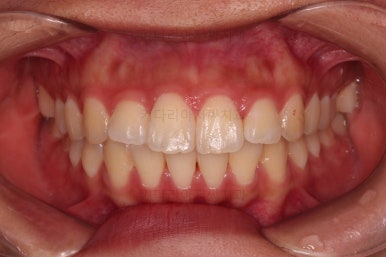

1. 초진 시 입안의 모습 평가

부산연산역치아교정 키다리아저씨치과에 처음 내원했을 당시의 입안의 모습이비다.

앞니 약간, 어금니쪽 약간 삐뚤어진 것, 그리고 위아래 앞니가 약간 뻗쳐 보이는 양상 이외에는 매우 가지런해 보여서 교정치료를 굳이 왜 하시려고 하지? 라고 생각될 정도의 치열 상태였습니다.

큰 문제는 없었지만, 약간 삐뚤었던 치열이 가지런하게 정렬이 잘 되었고요.

맞물림도 매우 좋고, 뻗친 앞니 각도도 매우 좋아졌습니다.

입 안의 모습만 보면 최상급의 마무리가 되었고요.